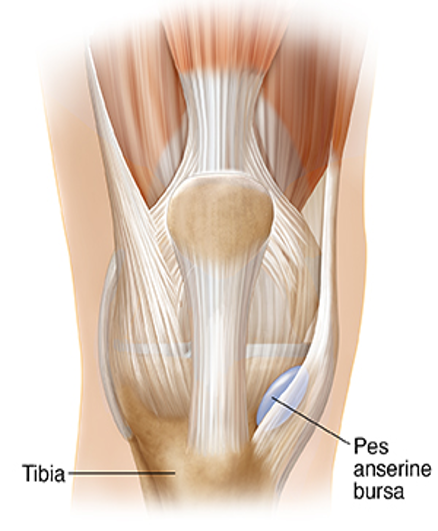

Knee: Pes Anserine Bursitis

Etiology: inflammation of the pes anserine bursa

Remember it is deep to the gracilis, sartorius, and semitendinosus tendons at the lower medial knee

Common symptoms/ complaints:

Localized pain medial knee just below joint line

Mild swelling occasionally

Commonly seen in runner (hills/stairs)